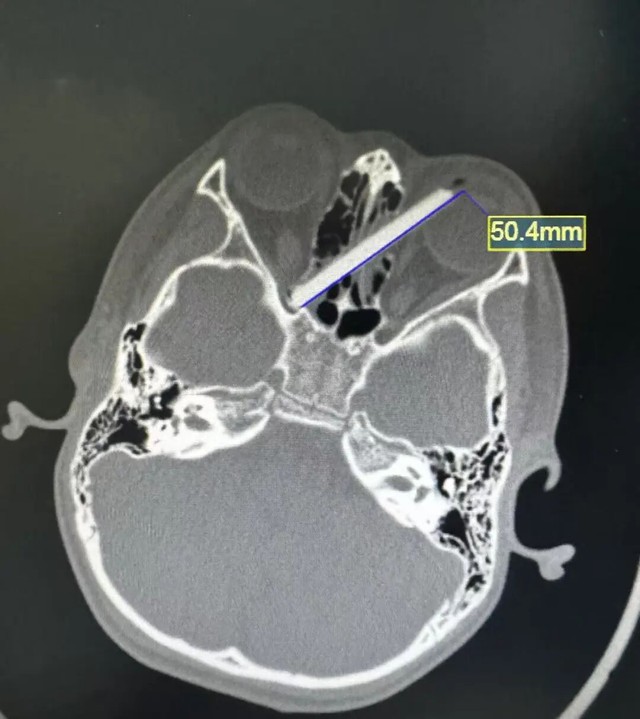

Hình ảnh chụp CT cho thấy chiếc đũa bị đâm vào mắt trái của đứa trẻ.

Tại bệnh viện, các bác sĩ lập tức chỉ định chụp CT khẩn cấp. Kết quả cho thấy phần đũa bị gãy đã mắc vào vùng mắt của bé.

Theo bác sĩ, dị vật nằm ở vị trí rất nguy hiểm, sát nhãn cầu và dây thần kinh thị giác, đồng thời đi qua khu vực hốc mắt và xoang mũi. Nếu không được xử lý kịp thời, dị vật có thể gây tổn thương thị lực và nhiều biến chứng nghiêm trọng khác.